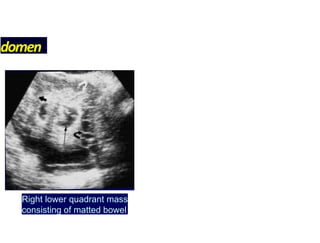

USGabdomen — Thickened bowelwall — Loculated ascites — Interloop ascites-club sandwitch sign — Mesenteric thickening hyperechoic >15mm — Lymph node enlargement — Pulled up caecum (Pseudokidney sign) 33

domen Right lower quadrantmass consisting of matted bowel